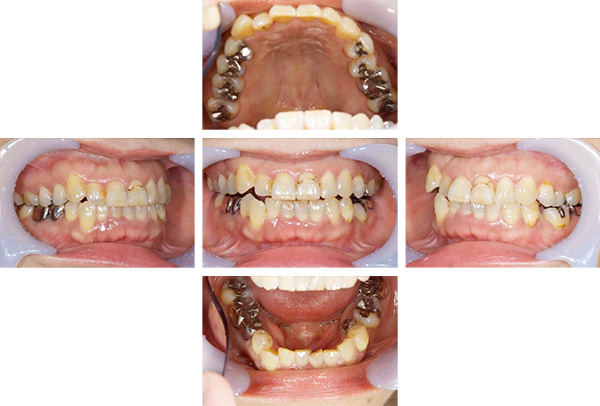

歯列矯正・インレー・クラウン症例

前歯が黒っぽいのが気になる、

悪いところは全部治したい

年齢 54代女性

主訴 歯をきれいにしたい

治療

期間

4年

費用 セラミックインレー 12本

660,000円

オールセラミックプレミアムクラウン 3本

495,000円

矯正 874,900円

計 2,029,900円(税込)

※全て税込となります。

症例写真(治療前)

担当医師所見

治療前:

八重歯が目立ちます。また銀歯もおおく、見た目が気になります。虫歯も散見できます。

レントゲン写真(治療前)

根の治療を3本すでに治療されています。1本根の奥の詰め物が疎になっていますので、根の部分の再治療も行う必要がありそうです。銀歯の中で虫歯になっているものもあります。

治療中

矯正装置をつけています。だんだん八重歯が動いてきているのがわかります。今回のケースでは、抜歯を行わずに矯正ができました。

症例写真(治療後)

治療後:

矯正治療と虫歯の治療すべて終わったときの写真になります。見た目も最初の頃とは全く違いますし、お口の中もすごく綺麗です。

方針

まずは虫歯の治療を行い、被せ物をする部分は仮歯をいれて矯正を行う。矯正終了後、仮歯の部分を最終的な被せ物に変えていく。また気になっていた銀歯もセラミックに変えて終了となった。

内容

セラミックインレー、オールセラミックプレミアム、矯正

特記

事項

虫歯の治療によって歯が一時的に染みるようになる可能性があります。また、歯を抜かずに矯正を行っていますが、全ての方で歯を抜かずに矯正ができるわけではありません。

治療リスク・副作用

・詰め物を銀歯からセラミック等のインレーに変えると、歯がしみることがある

・被せ物をやりかえる時は中で大きく虫歯になっていたり、歯が割れている場合は抜歯になることもある

・インプラント治療は骨と結合するのに期間がかかるが、個人差がある

・ホワイトニング後は歯がしみることがある

・詰め物、被せ物をする時は自分の歯を削ることになります